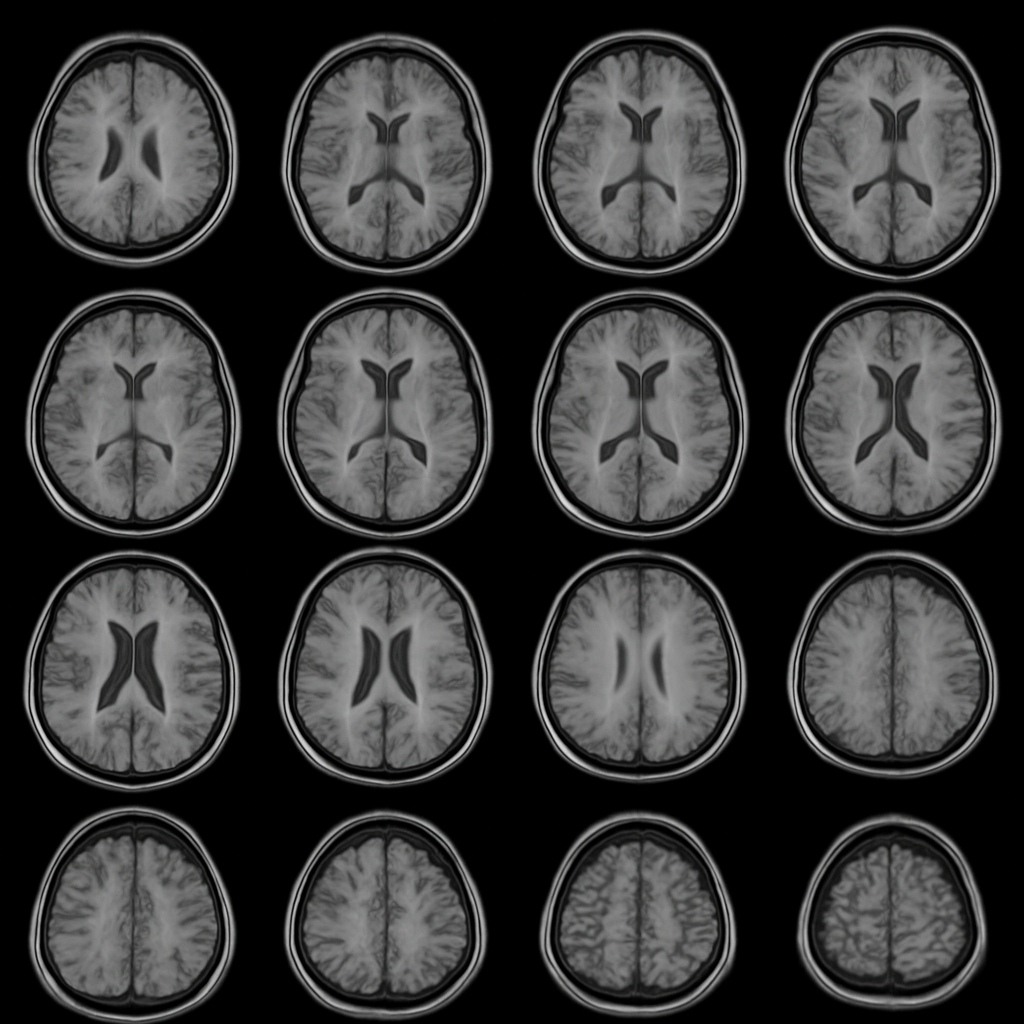

Figure 1: Multi-slice brain activity captured via fMRI. These axial slices serve as input to the automated analysis pipeline, which performs task-aligned GLM analysis to detect regions showing statistically significant activation.

A well-specified input includes the fMRI volume dimensions (e.g., 20x20x10 voxels), number of timepoints (e.g., 100 TRs), and accompanying event files that encode experimental timing.